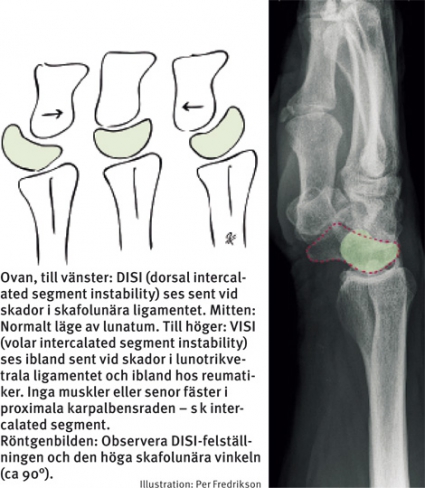

Eftersom scaphoideum har en stark inneboende strävan att rotera i volarflexion, medan triquetrum tvärtemot tenderar att rotera i dorsalextension, föreligger en inbyggd spänning mellan de tre benen i den proximala karpalbensraden. Detta bidrar till carpus stabilitet – i princip på samma sätt som en spiralfjäder i metall tar upp och fördelar krafter och spänningar. Detta förklarar också hur de klassiska felställningarna DISI (dorsal intercalated segment instability) och VISI (volar intercalated segment instability), som man ser sent vid interkarpala ligamentskador, uppkommer.

Klassificeringen DISI/VISI utgår från lunatums felställning. Om skafolunära ligamentet går av kommer scaphoideum att »fritt« kunna rotera i volarflexion, medan lunatum, som fortfarande har förbindelse med triquetrum, tvingas följa detta ben i dorsalextension – DISI uppkommer!

Vid kontinuitetsavbrott i lunotrikvetrala ligamentet blir situationen den omvända, och en volar felställning, VISI, uppstår när lunatum dras med av scaphoideums flexion. Lunatums position ger därigenom vägledning till vilket ligament som är skadat.

Observera dock att för att en sådan kraftig rotation av scaphoideum eller triquetrum ska uppkomma krävs att även övriga ligament som fäster i dessa ben (s k sekundära stabilisatorer) ska vara skadade eller successivt sviktar och tänjs ut. Denna senare utveckling med uttänjning av övriga ligament tar ofta lång tid och är orsaken till att DISI eller VISI mycket sällan ses i det akuta eller subakuta skedet.

Akut tagna röntgenbilder, även med provokation, utesluter alltså inte allvarlig ligamentskada. Alla ligamentskador är initialt dynamiska, dvs framträder enbart vid belastning och provokation. Med tiden blir de statiska. DISI/VISI kan då ses som permanent felställning. DISI innebär radiologiskt indirekt samtidigt att vinkeln mellan scaphoideum och lunatum på sidobilden överstiger 60–80°, jämfört med en normal vinkel på 30–60°. I en sådan situation framträder också en s k skafolunär dissociation. Det skafolunära avståndet på frontalbilden ska normalt sett vara mindre än 3 mm.